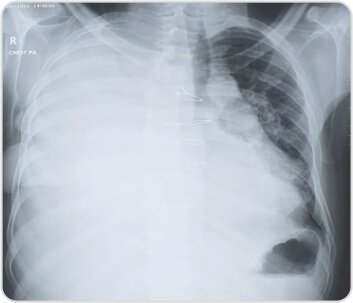

Pre procedure chest radiographs showingmassive right pleural effusion